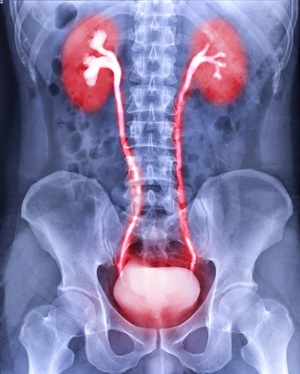

Cancer of the ureter is rare and occurs in the tubes that carry urine from the kidneys to the bladder and can also be found in the renal pelvis, the area where urine collects and is funneled into the kidney. Because ureter cancer is rare, you need urology experts who are experienced in treating this type of cancer.

Advanced testing by experienced urologists and uroradiologists is essential for a diagnosis of ureter or renal pelvis cancer. We use the latest imaging and digital ureteroscopy to make an accurate diagnosis.

You have access to the most advanced imaging technology at Hackensack Meridian Health. Our uroradiologists are radiologists who specialize in diagnosing conditions of the urinary tract, including cancer of the ureter and renal pelvis. Imaging tests may include:

- CT Urography – CT with contrast dye to outline the structures of the kidneys, ureters and bladder

- Intravenous Pyelogram – series of X-rays taken with contrast dye to outline the structures of the kidneys, ureters and bladder